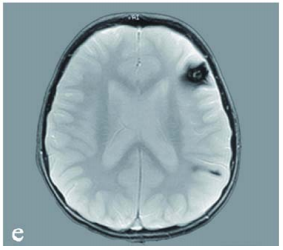

经抗水肿治疗后,患儿临床状况趋于稳定,神经症状短期内有所改善。但后续MRI检查显示原发病灶已增长至4×3.5×3cm,同时在左额叶及顶叶发现继发性致痫灶,病理类型同为海绵状血管瘤。

多发病灶提示存在家族遗传可能。基因检测证实患儿及其母亲均携带CCM1基因新发突变。母亲MRI虽显示多发性海绵状血管畸形病灶,但未见临床症状表现。

由巴教授主刀完成病灶全切手术,术中应用体感诱发电位及脑干听觉诱发电位监测,结合神经导航技术实现精准切除。术后十日MRI证实病灶完全切除,脑干受压解除,第四脑室形态恢复正常。患儿神经功能持续改善,后续接受系统化神经康复治疗。